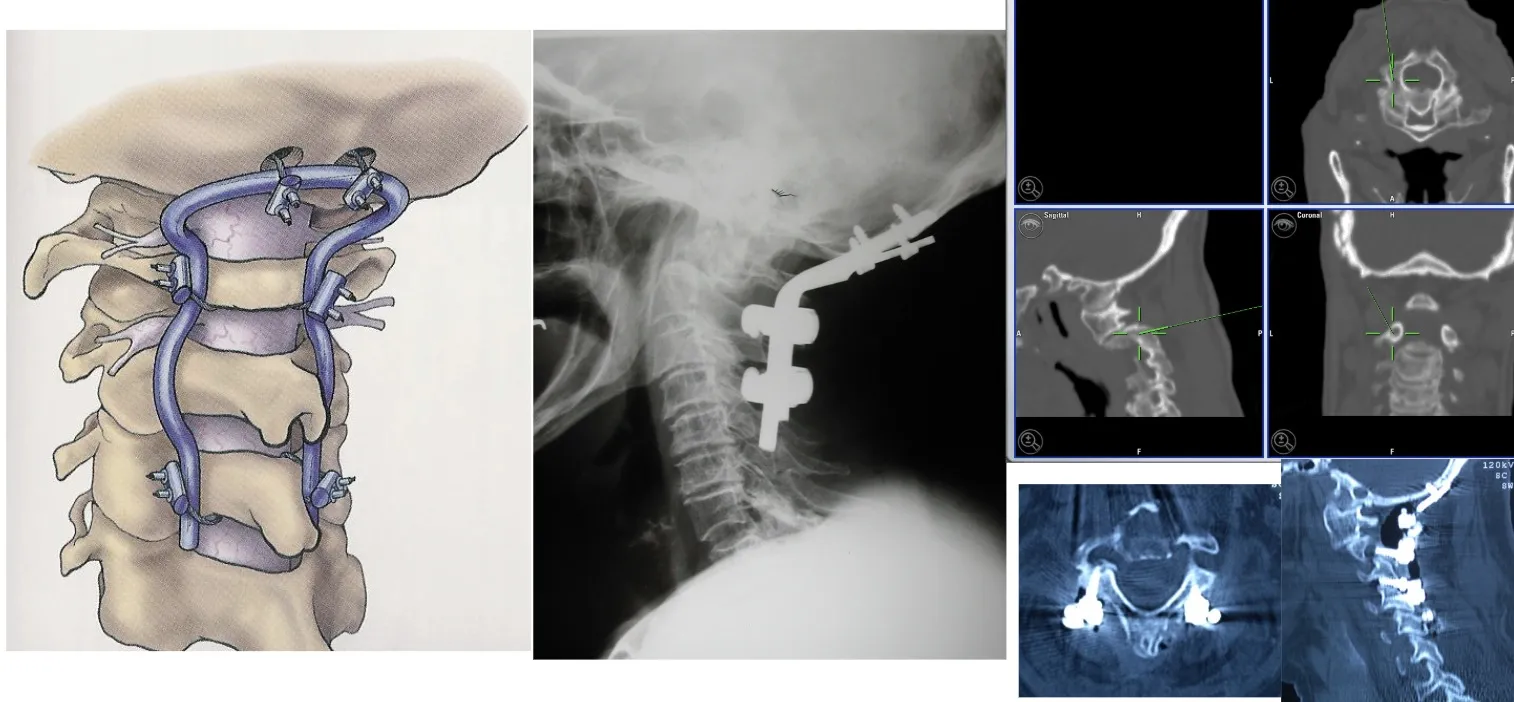

En estos casos, es posible utilizar sistemas de fijación que permiten anclar el cráneo a la columna cervical, con el fin de mantener la estabilidad y evitar el colapso producido por la invasión tumoral de la vértebra afectada. Estas fijaciones, realizadas mediante placas, tornillos y barras especialmente diseñadas, aseguran la continuidad estructural entre el cráneo y la columna, garantizando la correcta alineación y protección de las estructuras neurológicas.

También es posible acceder a la columna cervical por vía anterior y resecar una vértebra completa cuando la lesión lo requiere. Este abordaje permite eliminar totalmente el cuerpo vertebral afectado, descomprimir la médula espinal y, posteriormente, reconstruir y estabilizar la zona mediante injertos óseos o dispositivos protésicos que restituyen la alineación y la función de la columna.

Otra opción es acceder por vía posterior, lo que permite realizar una fijación más sólida y estable mediante la colocación de tornillos y barras en los elementos posteriores de la columna. Este tipo de abordaje ofrece un mayor refuerzo estructural, especialmente útil cuando existe pérdida de sostén anterior o es necesario complementar una reconstrucción realizada previamente por vía anterior.